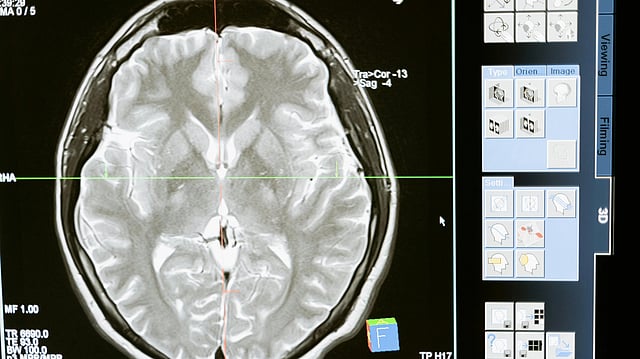

Following emergency treatment at Life Care Hospital, Dr. Bhutia was referred to Apollo Hospital for specialised care. There, medical evaluation identified a pre-existing brain aneurysm, a weakened area in a blood vessel in the brain that can expand and rupture, causing internal bleeding and neurological damage.1 The rupture of a brain aneurysm can lead to rapid deterioration in neurological function due to haemorrhage and increased intracranial pressure, often requiring intensive care and surgical intervention when detected early.

Brain aneurysms often remain asymptomatic until rupture, which makes them difficult to detect early without imaging studies such as MRI or CT angiography. Rupture can cause sudden loss of consciousness, severe headache, and increased risk of fatality. 1

A brain aneurysm is a focal dilatation in the wall of a cerebral artery due to structural weakening. Small aneurysms may be asymptomatic and undetectable without imaging, but when they rupture, they can lead to subarachnoid haemorrhage, bleeding into the space around the brain, which is a serious, life-threatening condition requiring immediate medical attention. Symptoms of rupture often include abrupt loss of consciousness, severe headache, nausea, and neurological deficits. Rapid resuscitation, advanced imaging, and neurosurgical or endovascular interventions can be lifesaving when applied swiftly. However, the risk of mortality and morbidity remains high, especially in spontaneous ruptures.